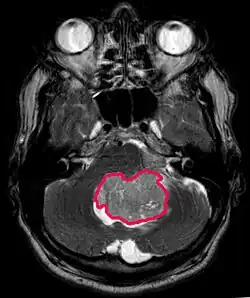

Tento nádor je typický pro zadní jámu, kde je lokalizován v obou hemisférách mozečku nebo v cerebelární vermis. Protože je invazivní a rychle roste, obvykle se šíří do jiných částí centrálního nervového systému (CNS) prostřednictvím CSF a může infiltrovat dno blízké čtvrté komory a mozkových blan. Vzácně se mohou objevit další metastázy do CNS. Když se objeví malignita, symptomy zahrnují ztrátu rovnováhy, nekoordinovanost, diplopii, dysartrii a v důsledku postižení čtvrté komory, což často vede k obstrukčnímu hydrocefalu, bolesti hlavy, nevolnosti a zvracení a nestabilní chůzi.

MRI obvykle ukazuje masivní lézi zvyšující kontrast zahrnující cerebellum. Jak již bylo zmíněno výše, meduloblastom má vysoký sklon k lokální infiltraci leptomeningů a také k šíření přes subarachnoidální prostor, zahrnující komory, mozkovou konvexitu a leptomeningeální povrchy páteře. Následně je nutné uvést do rezonance celou kraniospinální osu.